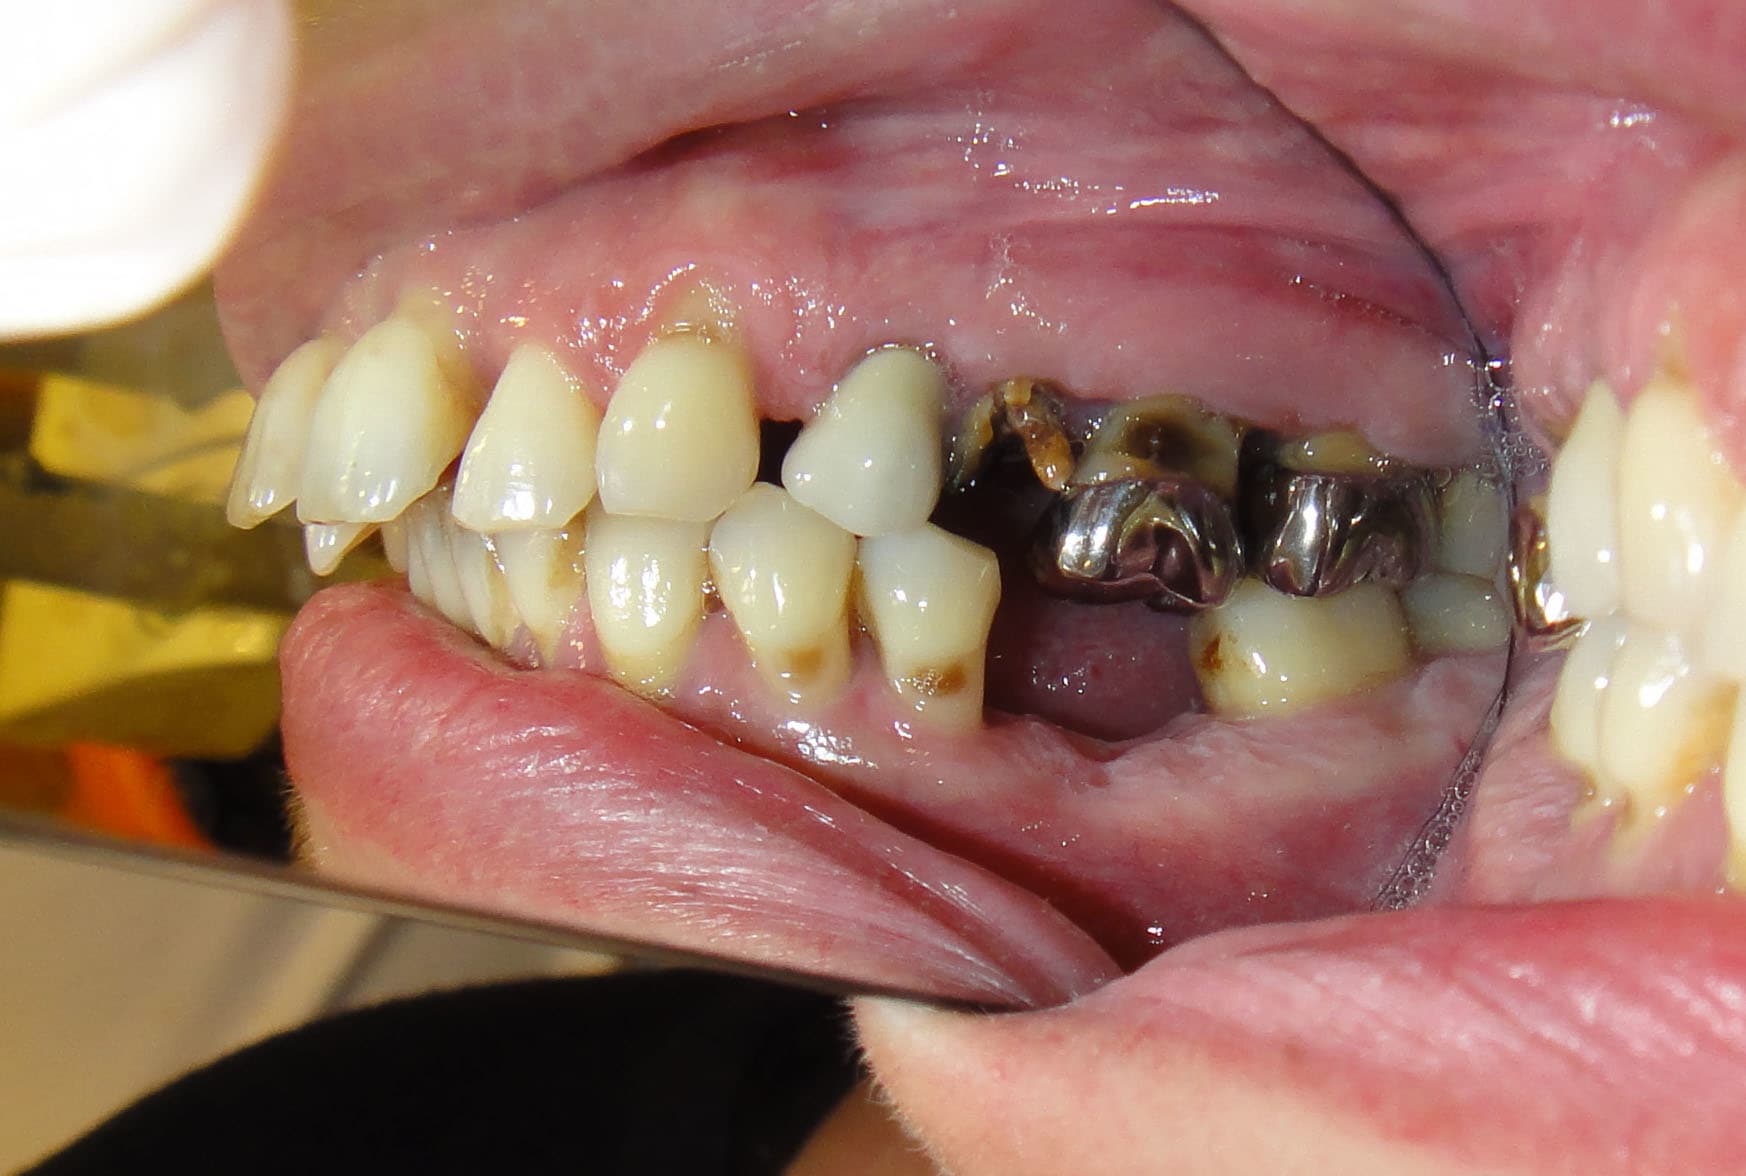

Le temps qu'elle se décide à faire quelque chose on se retrouve en 2013 avec cette photo du secteur antérieur.

L'occlusion est en classe II +++.

Les années passent avec toujours autant de cigarettes, et elle revient me voir en juillet 2017 avec un soucis esthétique au niveau de sa 12 plus les crochets du stellite qu'elle trouve très moches (et accessoirement 2 prémolaires en bas qui ne tiennent plus)